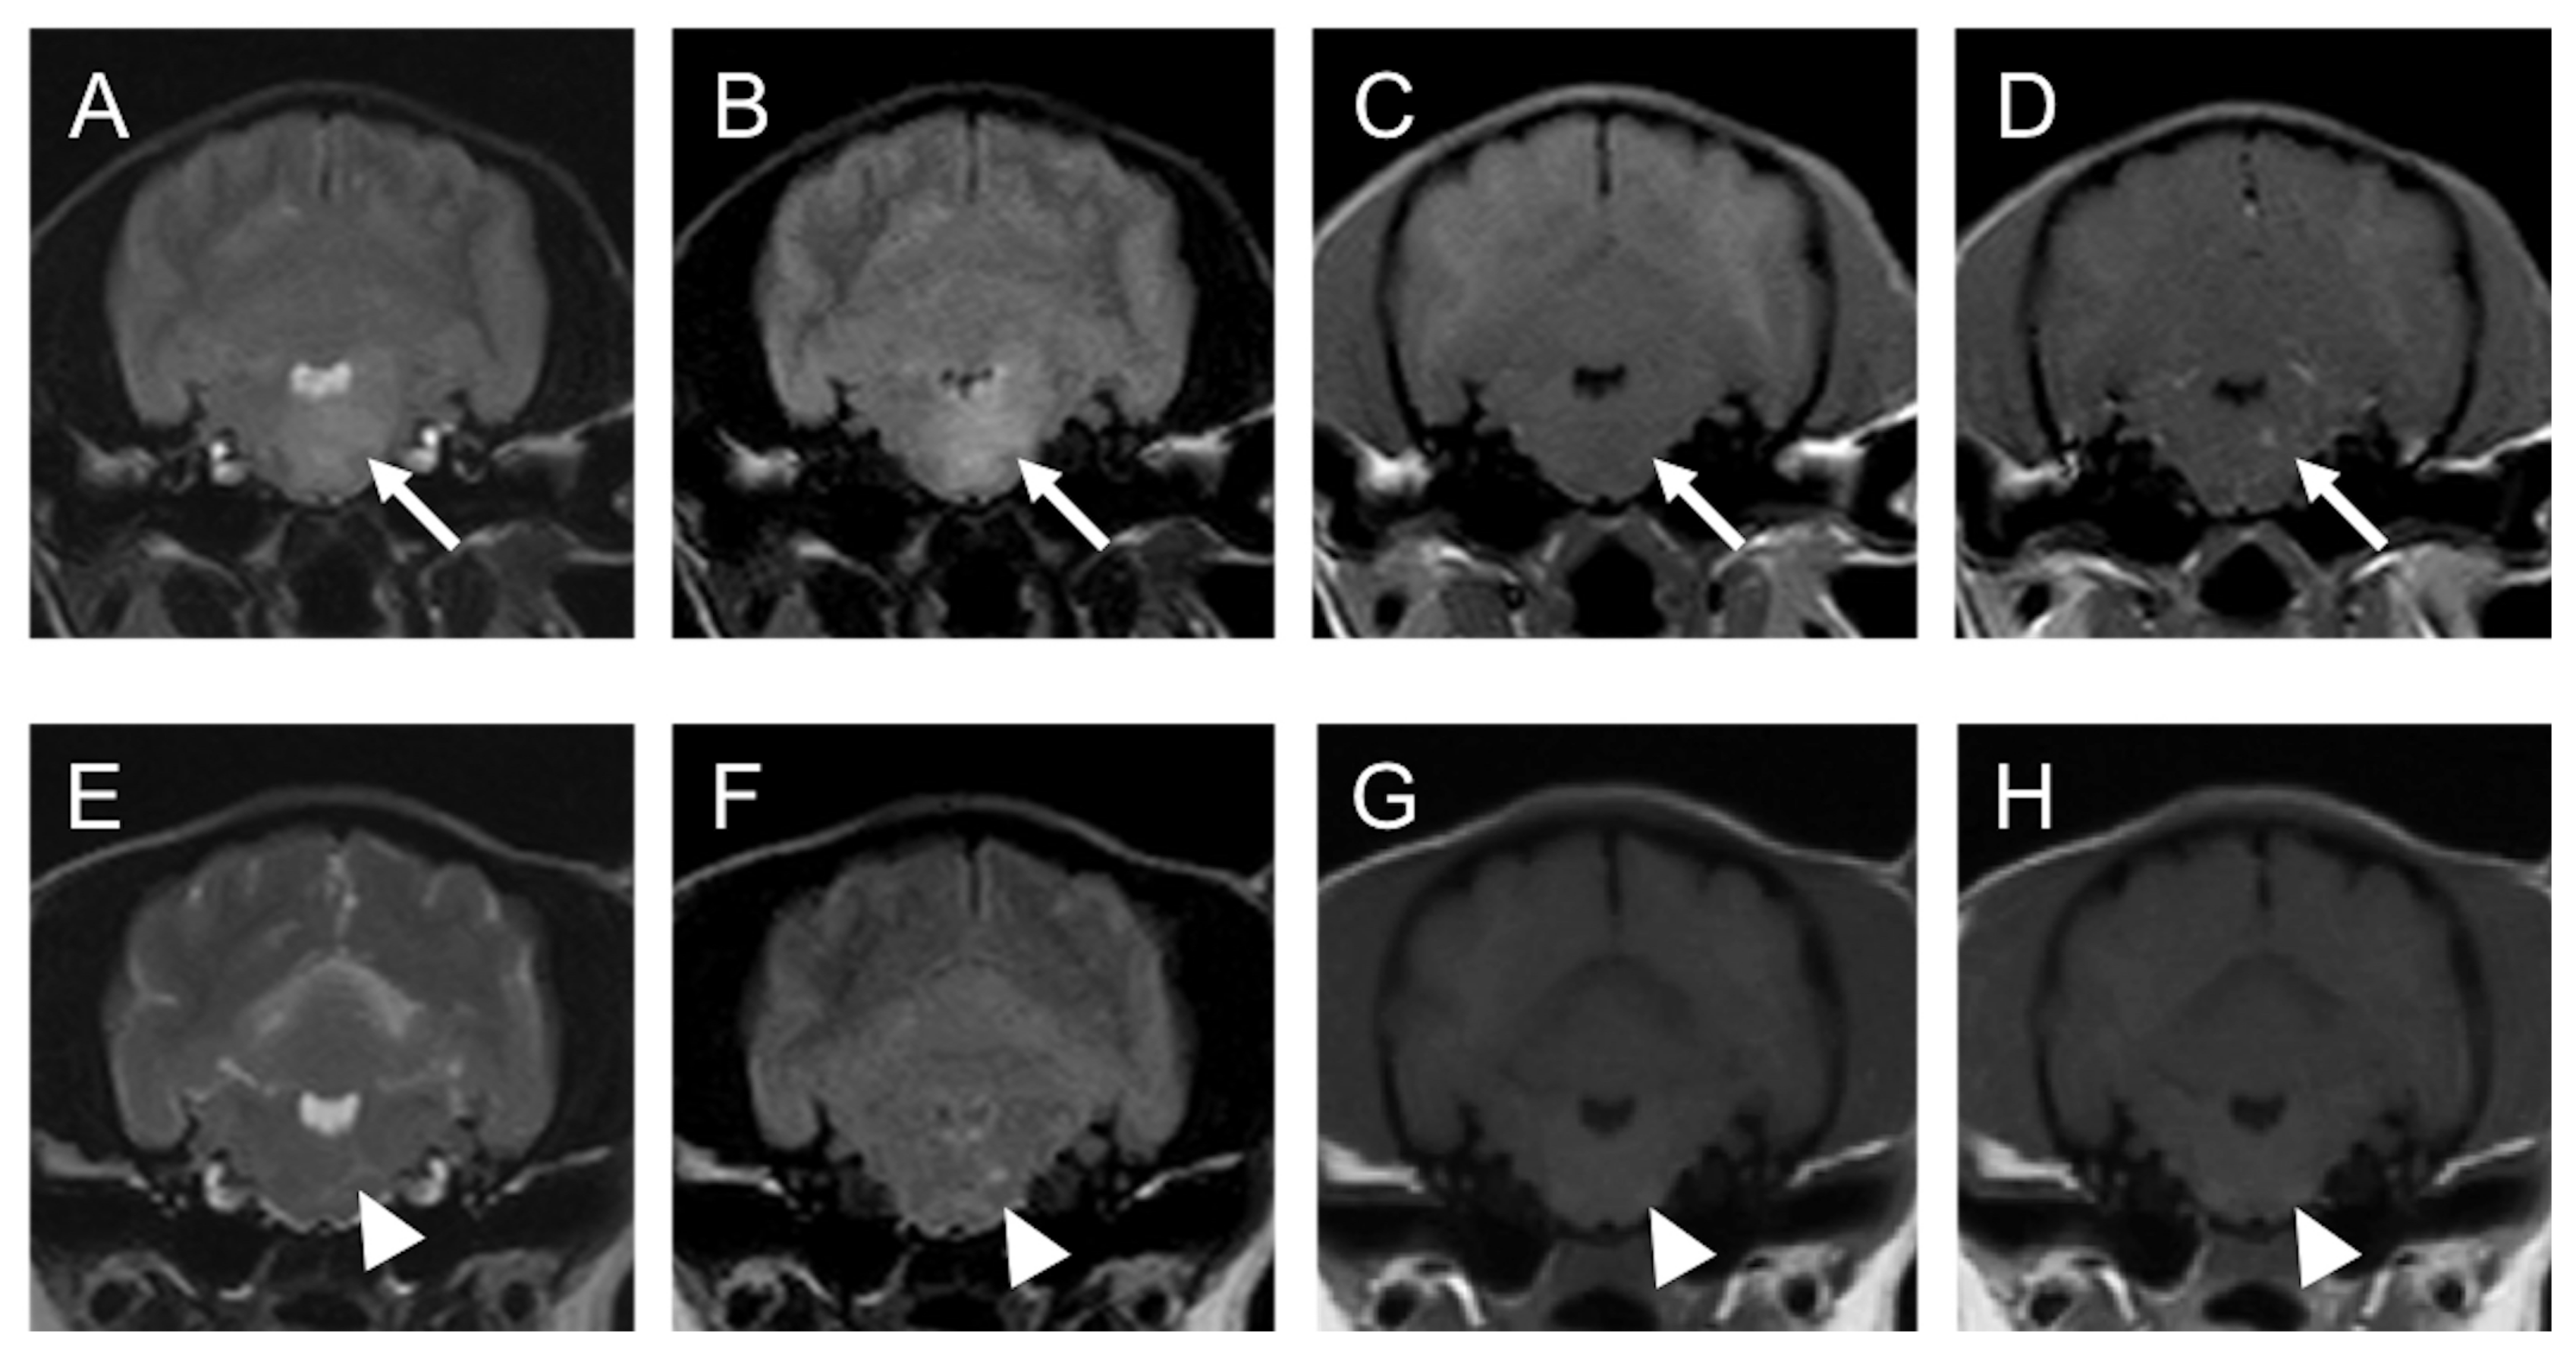

2.1. Case 1

2.2. Case 2